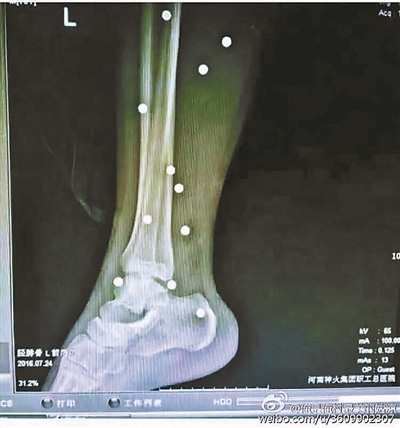

傷者體內(nèi)取出的鋼珠

爆炸導(dǎo)致鋼珠遍布傷者身體各處

黃明的伯伯對(duì)北青報(bào)記者表示,由于黃明直接踩到了爆炸物,所以傷情最為嚴(yán)重,“他的腿被炸斷,身體內(nèi)被炸進(jìn)了40多顆鋼珠。手術(shù)后已經(jīng)從體內(nèi)取出29顆鋼珠,還有十多顆鋼珠沒(méi)有取出來(lái)。”根據(jù)黃明的入院記錄,他全身有多處爆炸傷,且全身多處異物存留。

爆炸發(fā)生時(shí),陳浩的位置與黃明靠得很近,因此也受傷較重。他告訴北青報(bào)記者,經(jīng)過(guò)10多個(gè)小時(shí)的手術(shù)后,醫(yī)生從他身體里取出了12顆鋼珠。目前,他和黃明兩人經(jīng)過(guò)手術(shù)后,已從重癥監(jiān)護(hù)室轉(zhuǎn)至普通病房。其余三人中,陳剛的臀部受傷,當(dāng)天晚上在醫(yī)院清理完傷口后便回了家,而同行的兩名女生身上有一些擦傷。